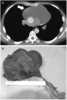

Congenital thymic cyst